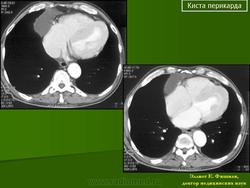

Киста перикарда.

киста перикарда

КТ

Визуализируется, как округлое образование перикарда с четкими контурами с минимальным содержимым жидкости и плохо контрастируемое.